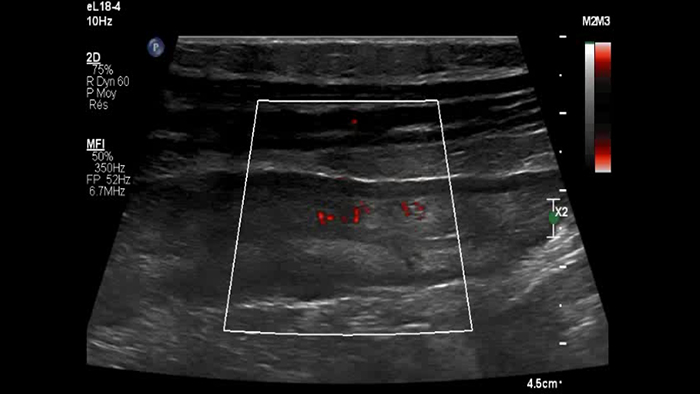

Est-ce si simple ? Probablement pas car 2 questions importantes restent en suspens : Les paramètres d’acquisition MFI doivent donc être adaptés à la réduction des artefacts sans masquer le micro-flux des vaisseaux. Les deux images suivantes de la même paroi intestinale sont obtenues avec des paramètres différents en termes de sensibilité du micro-flux et de détection de la vélocité. Après ajustement des paramètres, la deuxième image permet apparemment d’effacer les artefacts de mouvement (petites taches) tout en laissant les microvaisseaux pariétaux (images linéaires) clairement visibles. Il semble que cet ajustement ne soit pas toujours facile à obtenir pour valider la signification des images de micro-circulation de flux, et donc la densité des microvaisseaux, qui constitue l’information principale pour détecter une inflammation aiguë.